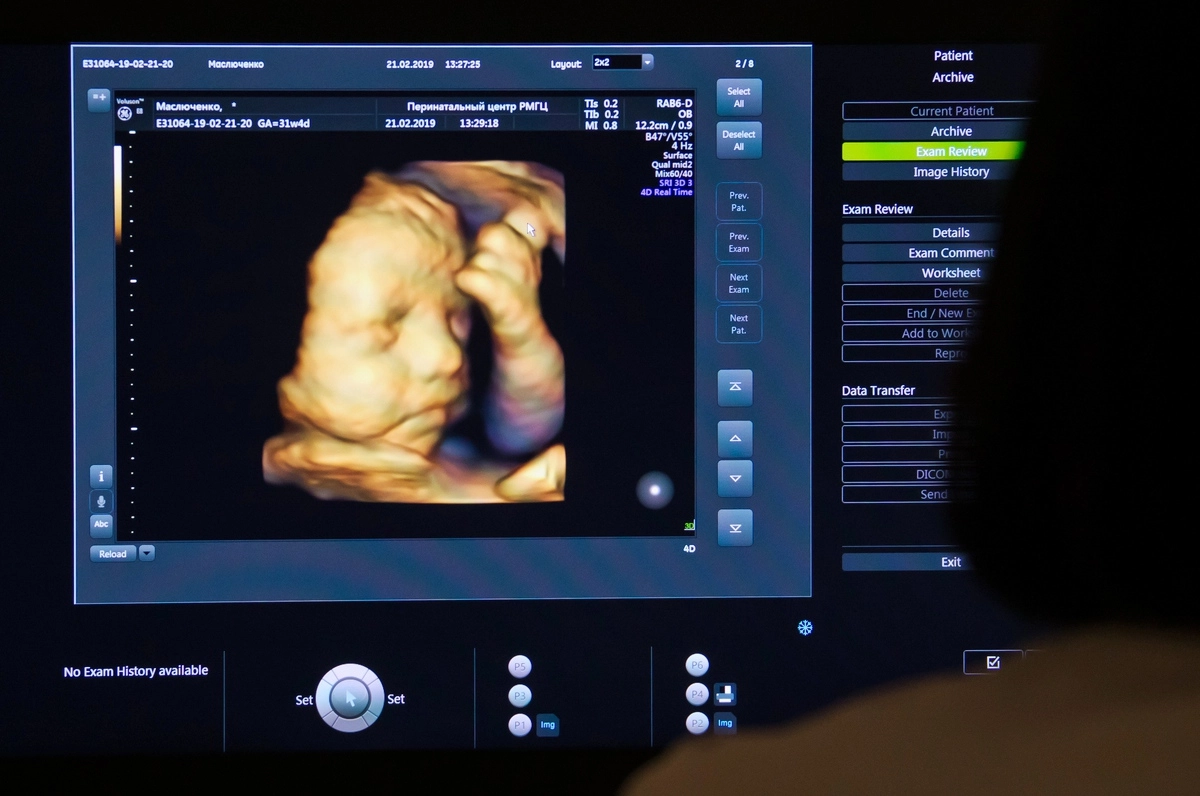

Скажу однозначно и сразу: аборт, из каких бы побуждений он ни проводился, — это убийство. Это остановка жизни. Хоть на разрешенных 12 неделях, хоть по медицинским показаниям в середине срока. Просто люди взяли и договорились, что вот до такой-то недели это «ничего страшного, там клеточки только формируются», а после, когда уже у плода есть нервная система, это якобы все, табу.

Для женщины — элементарно потому, что на начальной стадии беременности она ее не ассоциирует ни с собой, ни с ребенком. Даже если она и знает, что беременна, пока эта беременность — у нее в голове. А вот когда ребенок уже бьет ножками, и вдруг происходит форс-мажор и он теряется — это уже трагедия… Для тех, кто этого ребенка действительно желает.

Действие происходит внутри живота женщины с эмбрионом. Не просто так ребенка в медицинской среде называют ребенком только с восьмого месяца беременности. До этого он — эмбрион, потом — плод. Скользко, и легко на всем этом поскользнуться, согласна. Но не нужно сравнивать женщину, сделавшую аборт, с реальным убийцей, мотающим срок .